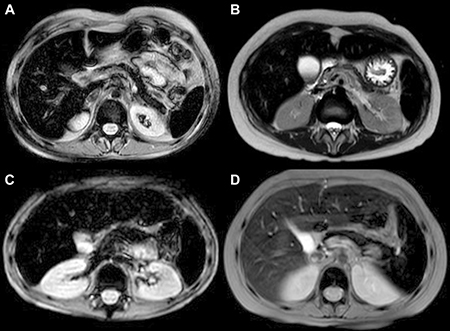

None of the 26 patients of the Group 2 presented with pathological iron concentrations in one or two organs: 20 patients presented with iron overload in three organs and six in all four organs analyzed (Figure 1A, 1B).

Figure 1: Abdominal MRI T2 FFE (fast field echo) sequences show hypointense liver, spleen, pancreas and bone signal due to abnormal iron deposition. (A, B) patients with intense transfusion regimen history; (C) patient with only 5 transfusion before MRI quantification of iron concentration; (D) patient treated with deferasirox: minor liver hyperintensity compared to spleen, pancreas and bone intensity.

This study showed that iron overload in patients with hematological malignancies is multifactorial, and not due exclusively to the intense transfusion regimen. Previously, systemic iron overload was studied only in transfusion-dependent patients with beta-thalassemia and sickle cell anemia. Iron overload in these patients was found to occur after transfusion of about 20 PRBC units [21],with iron deposited in parenchymal tissues after approximately 1 year of transfusions [22]. In contrast, our study found that nine of the 26 patients in Group 2 presenting with pre-transplant iron overload had received fewer than 20 PRBC units, with two receiving fewer than 10 units (Figure 1C). Furthermore, the time interval between the first transfusion and the appearance of multi-organ iron deposition in 15 of these 26 patients was shorter than 1 year. These findings suggest that patients with hematological malignancies develop iron overload faster, and after receiving fewer PRBC units, than patients with beta-thalassemia and sickle cell anemia.

The finding, that the percentage of patients presenting with pathological iron content at F3 was higher in Group 1 than in Group 2, was unexpected. It was likely due to the administration of chelation therapy only to patients in Group 2, not to those in Group 1. For outpatients the chelation therapy consisted of the administration of deferasirox, which more effectively removes iron from the liver than from other organs [25], resulting in a more rapid normalization of LIC than of BIC and SIC (Figure 1D). These results underscore the importance of organ-specificity of chelation therapy: “More importantly, dangerous heart iron accumulation and cardiac dysfunction can occur despite apparently superb control of liver iron during prospective longitudinal evaluation” [26].